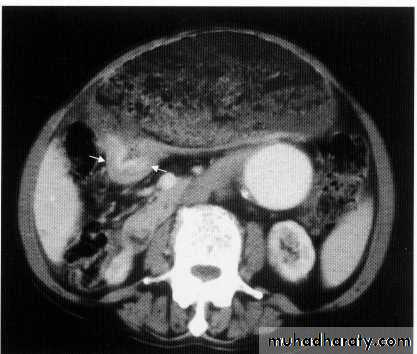

Ct scan carinal LAP